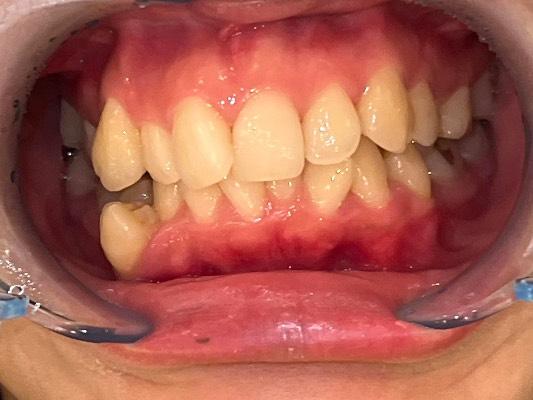

CASE 10

BEFORE

▶

AFTER

20代。 「前歯がデコボコしているのが気になる」「笑った時に歯並びが悪く見える」というお悩みでご来院。 仕事やプライベートで目立つワイヤー矯正は避けたいとのことで、透明なマウスピース矯正をご希望されました。